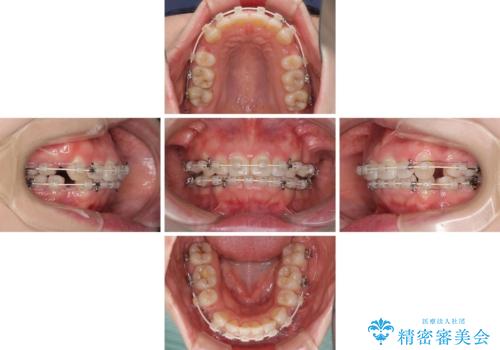

- 矯正装置

- 審美装置

- 前歯のデコボコを気にして来院された患者様です。

当初は口元の突出感はあまり気にされていない様子だったので、インビザラインによる非抜歯矯正をお勧めしたが、ふっくらとした口元を改善したいとのことで、積極的に口元の突出感を改善することとしました。

上下左右第一小臼歯4本の抜歯を行い、ワイヤー装置による矯正治療を行うこととしました。